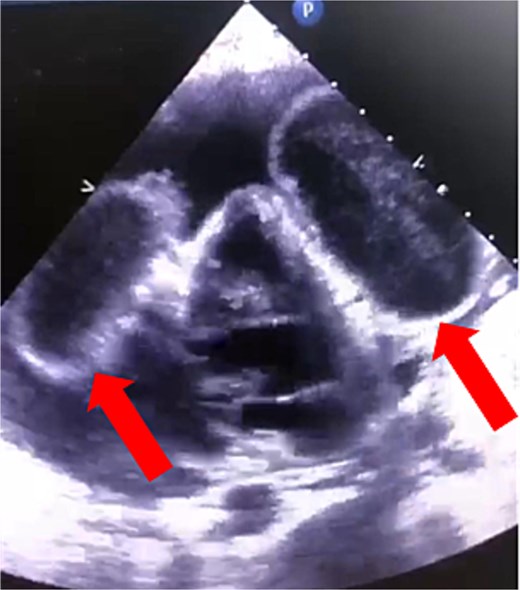

The patient’s condition worsened, developing a high fever, rapid breathing, and low blood pressure, leading to admission to the intensive care unit and treatment with medications to raise blood pressure. A full infection workup was negative. A computed tomography (CT) scan of the chest showed a large pericardial effusion measuring 5.5 cm in thickness and a small right heart chamber (Fig. 2). An echocardiogram revealed a normal left ventricle with an ejection fraction of 60%, but the right ventricle was compressed by a large oval-shaped structure inside the pericardial sac. The pericardial effusion measured 4.6 cm in thickness, and the inferior vena cava was dilated at 2.7 cm, with no heart valve regurgitation or blood clots inside the heart (Fig. 3).

Cardiac echocardiography showed that the right ventricle was compressed by an oval-shaped large intrapericardial structure representing the cysts (arrows).